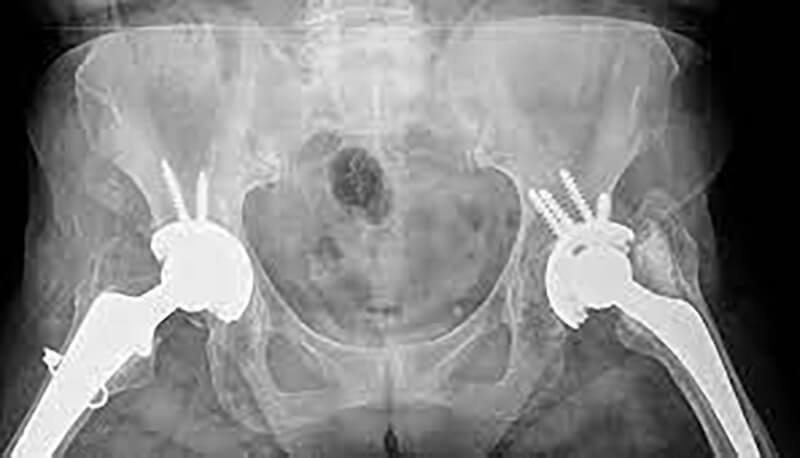

Η αρθροπλαστική ισχίου, γνωστή και ως χειρουργική επέμβαση αντικατάστασης ισχίου, είναι μια χειρουργική επέμβαση κατά την οποία μια κατεστραμμένη ή άρρωστη άρθρωση του ισχίου αντικαθίσταται με μια τεχνητή άρθρωση, που ονομάζεται πρόσθεση. Η πρόθεση έχει σχεδιαστεί για να μιμείται τη φυσική κίνηση της άρθρωσης του ισχίου, επιτρέποντας βελτιωμένη κινητικότητα και μειωμένο πόνο.

Η χειρουργική επέμβαση περιλαμβάνει την αφαίρεση των κατεστραμμένων ή άρρωστων τμημάτων της άρθρωσης του ισχίου και την αντικατάστασή τους με μια πρόσθεση από μέταλλο, πλαστικό ή κεραμικό.

Υπάρχουν δύο κύριοι τύποι αρθροπλαστικής ισχίου: η ολική αρθροπλαστική ισχίου, στην οποία αντικαθίσταται τόσο η μπάλα όσο και η υποδοχή της άρθρωσης του ισχίου και η μερική αρθροπλαστική ισχίου, στην οποία αντικαθίσταται μόνο η μπάλα ή η υποδοχή.